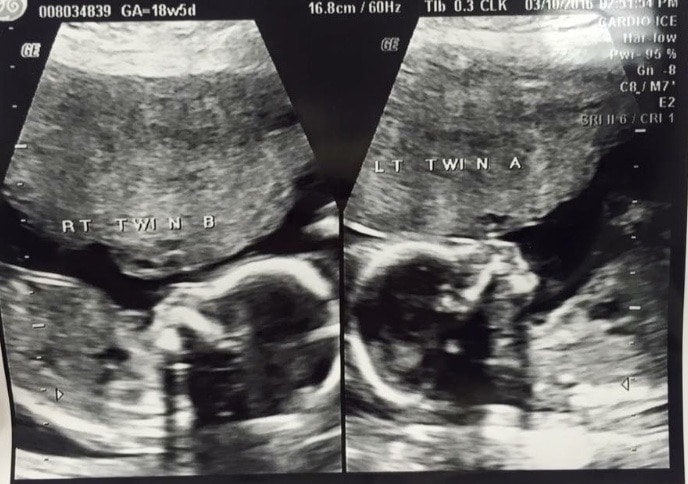

Ultrasound Photos at 18 Weeks Pregnant With Twins